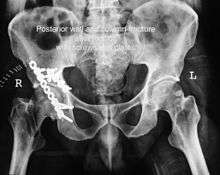

Posterior column fracture

Cause: as with posterior wall injury, this also occurs due to dash board injury.

Associated injury: There could be associated fracture of the posterior wall making this associated variety of fracture. The broken bone piece may injure the important Sciatic nerve causing paralysis of the foot, may or may not recover depending on the extent of injury to the nerve.

How to diagnose: Best seen in iliac oblique and obturator oblique views

CT scan helps in identifying impaction of bone pieces and if there are pieces in the joint

Treatment: if the femur head is dislocated, it should be reduced as soon as possible, to prevent damage to its blood supply. This is preferably done under anaesthesia, following which, leg is kept pulled by applying traction to prevent joint from dislocating.

The final management depends on the size of the fragment(s), stability and congruence of the joint.

In some cases traction for six to eight weeks may be the only treatment required

If the fragments do not fall into place, or if there are bone pieces in the joint, or if the joint is unstable, surgical fixation using screw(s) and plate(s) is performed

Post-surgery treatment: depending on the stability achieved, the person may be allowed standing and walking with help of support for about six to eight weeks.

Full function may return in about three months.

Complications: Sciatic nerve injury and stoppage of blood supply to femoral head at the time of accident or during surgery may occur. Deep vein thrombosis and pulmonary embolism are other complications that may occur in any type of injury to the acetabulum.